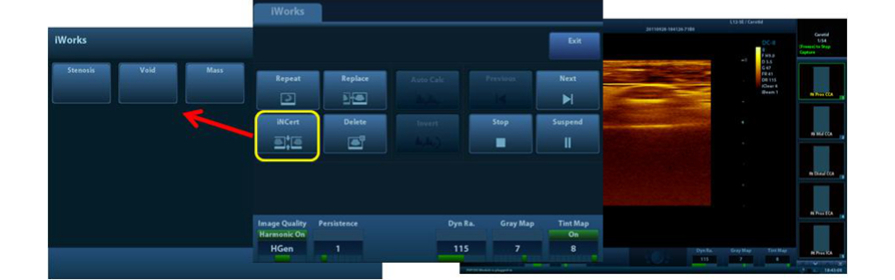

iWorks?

Uno strumento intelligente che consente di concentrarsi di pi├╣ sul paziente. Permette di ridurre notevolmente i tempi di scansione paziente attraverso standardizzazione e capacit├Ā definite dall'utente.

Auto IMT (Intima-Media Thickness)

Misurazione automatica dello spessore parietale anteriore e posteriore che consente di rilevare con precisione le condizioni della carotide.